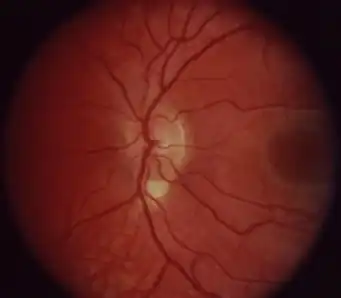

| Coloboma in a 16-year-old female | |

Right fundus with small coloboma at the inferior edge of the nerve that is vertically elongated.

Right fundus with small coloboma at the inferior edge of the nerve that is vertically elongated. Type 5 disc involvement in coloboma of choroid-left eye